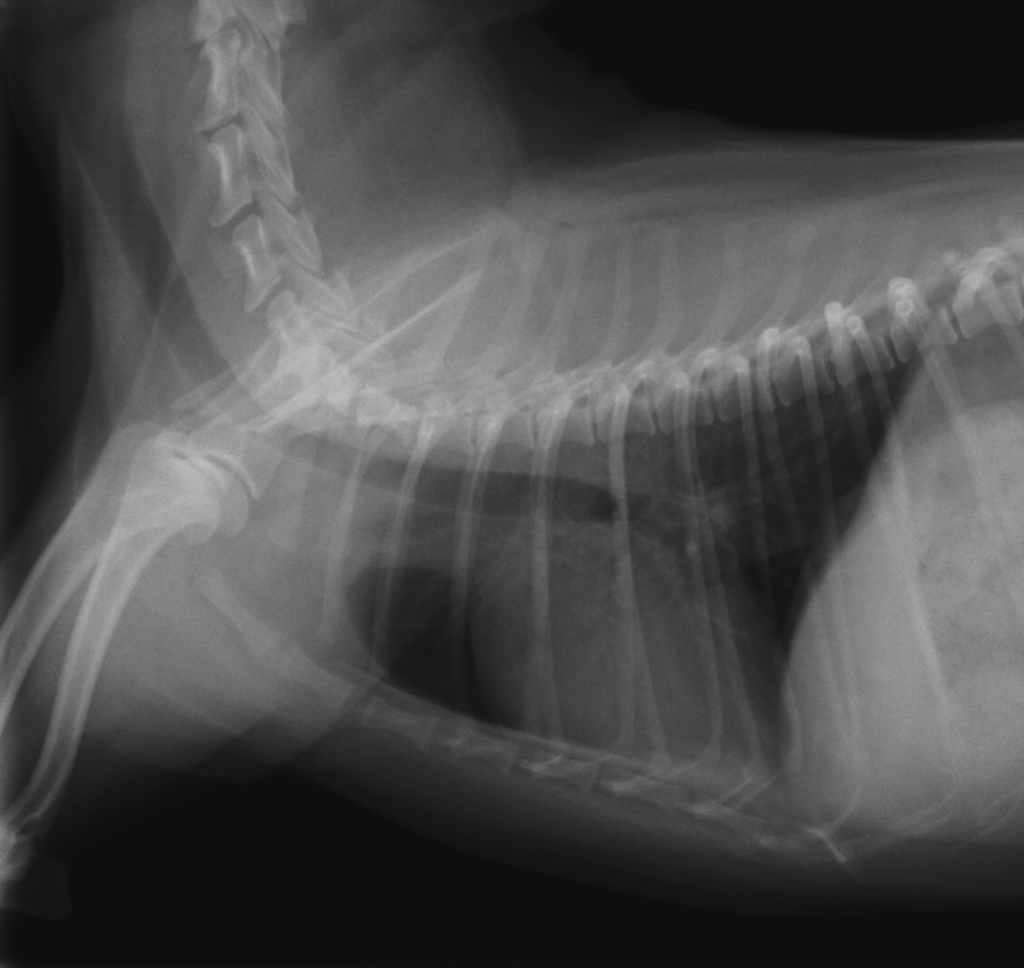

レントゲン検査では、大きく丸くなった心臓が確認できます。